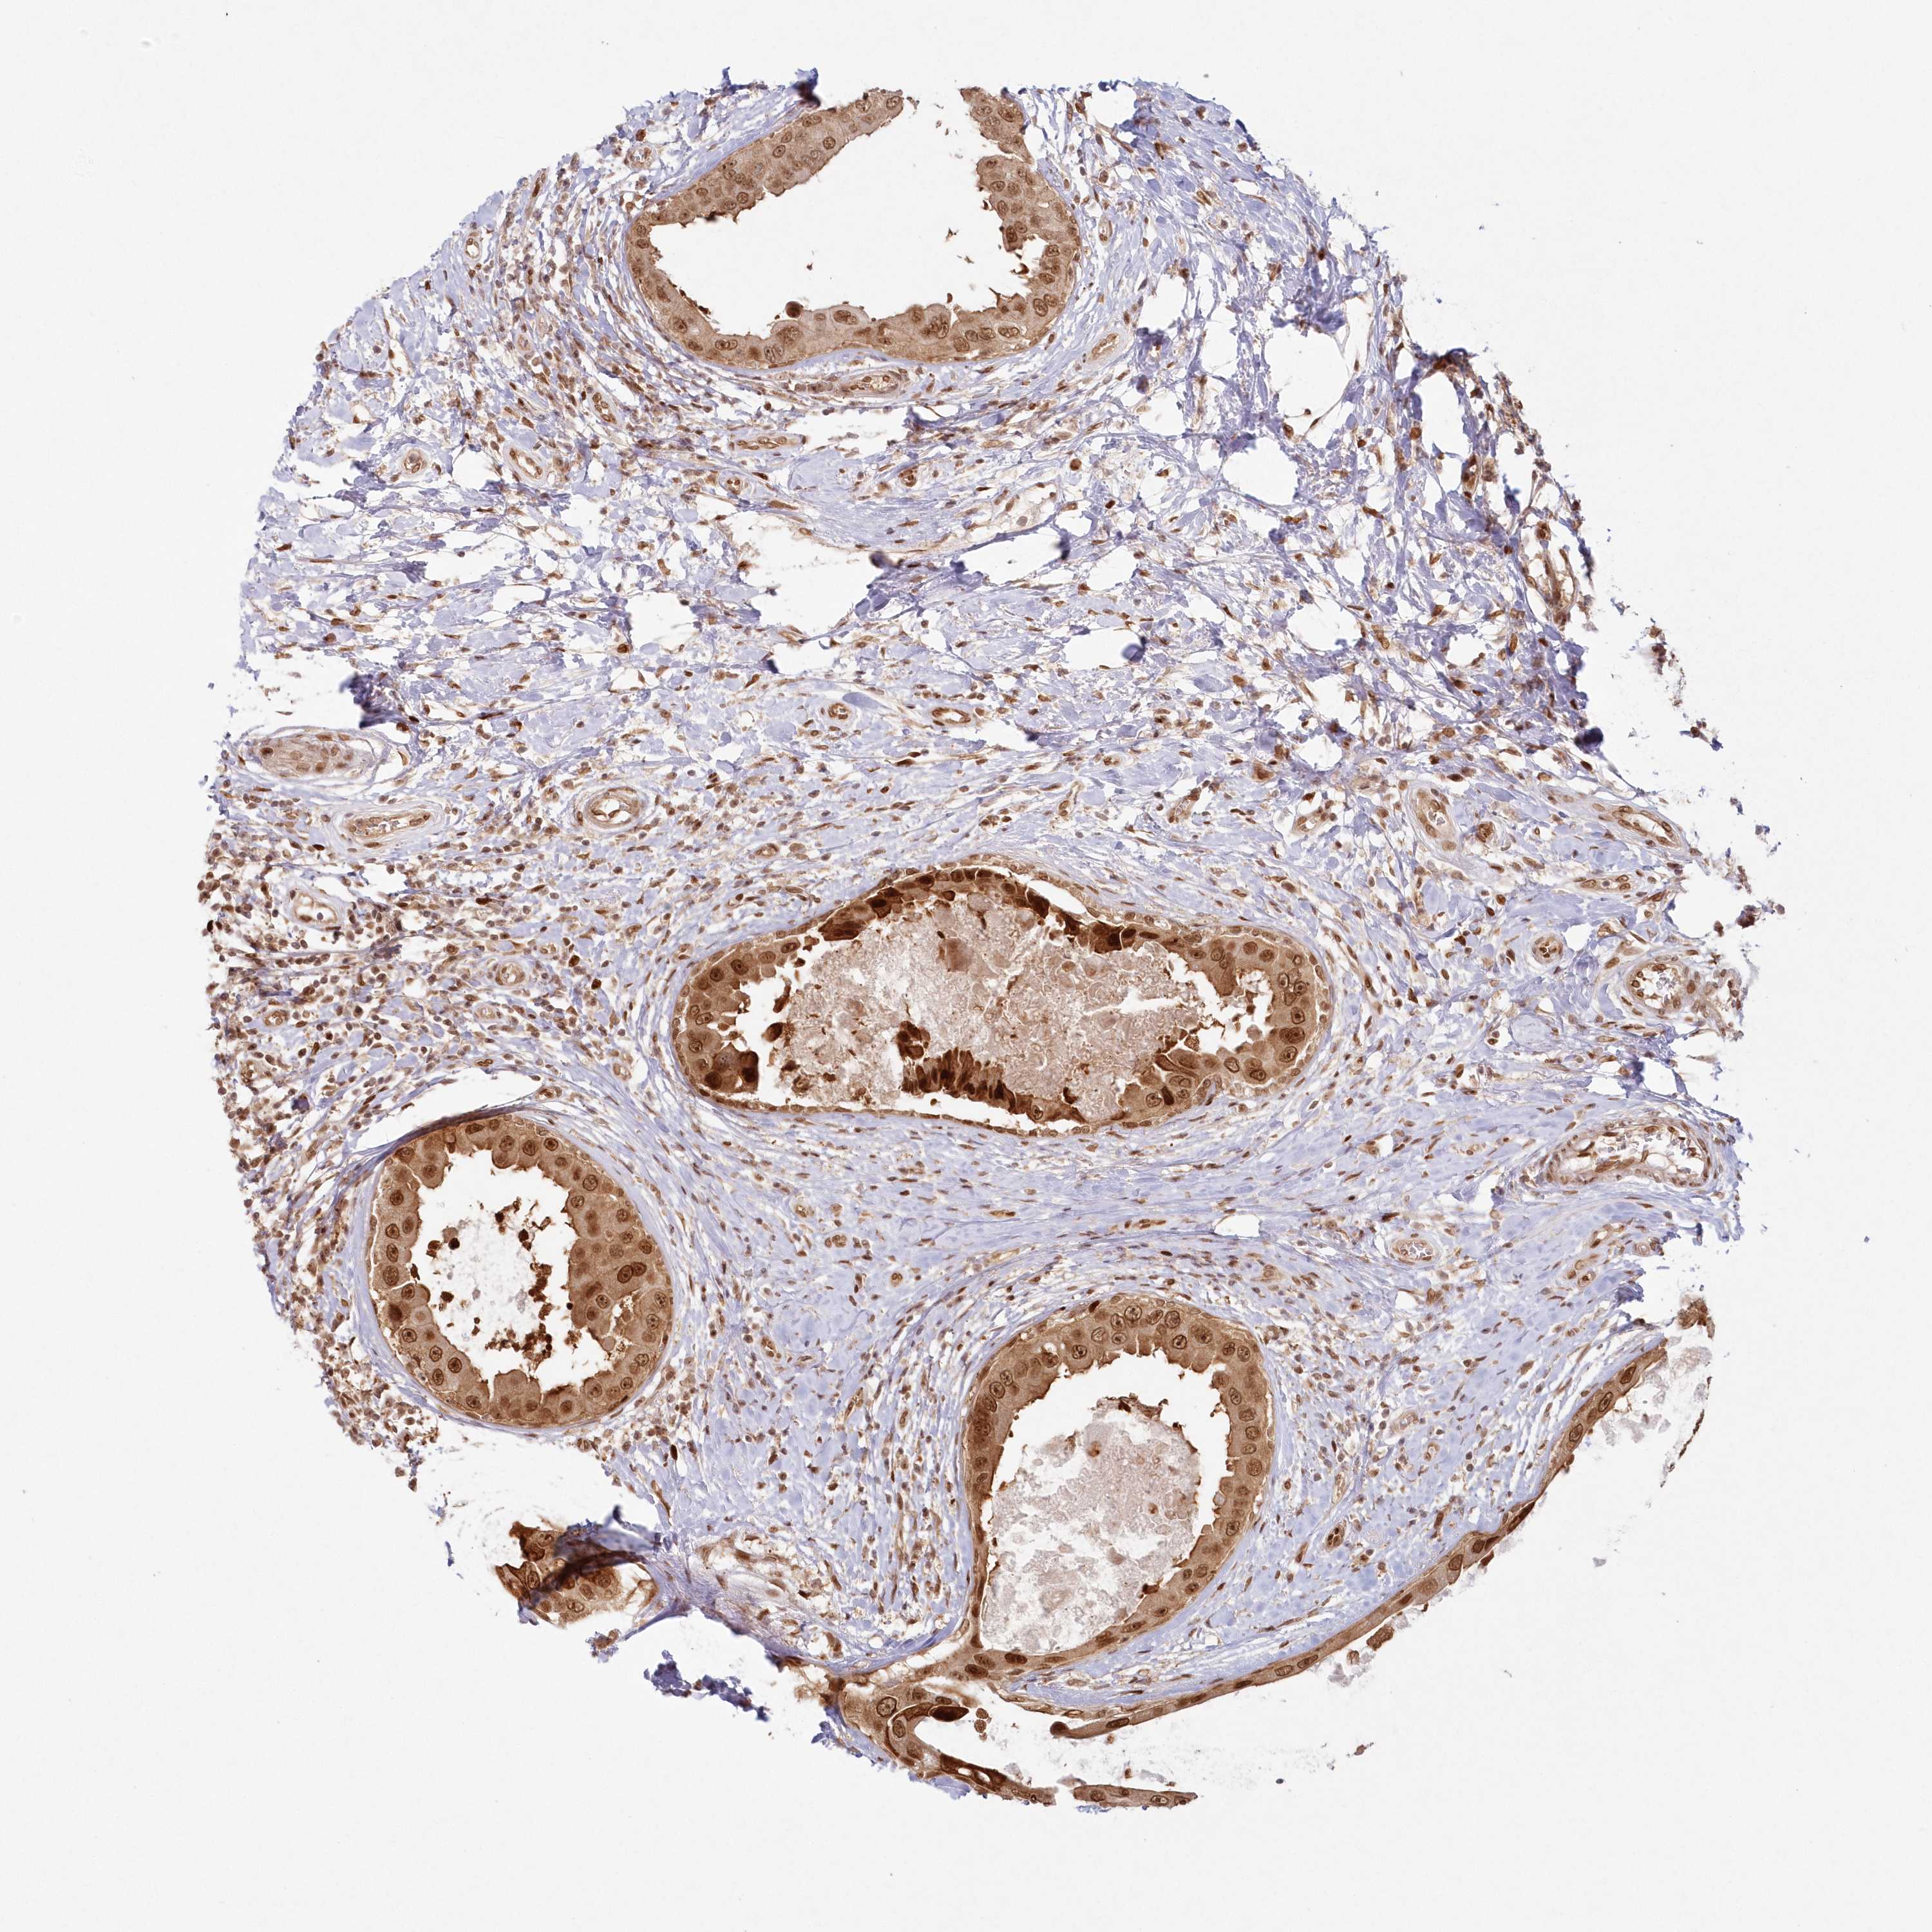

CANCER BREAST CANCER Show tissue menu

BRCA TCGA BRCA VALIDATION PROTEIN EXPRESSION

Breast cancer

Human cancer

Breast invasive carcinoma